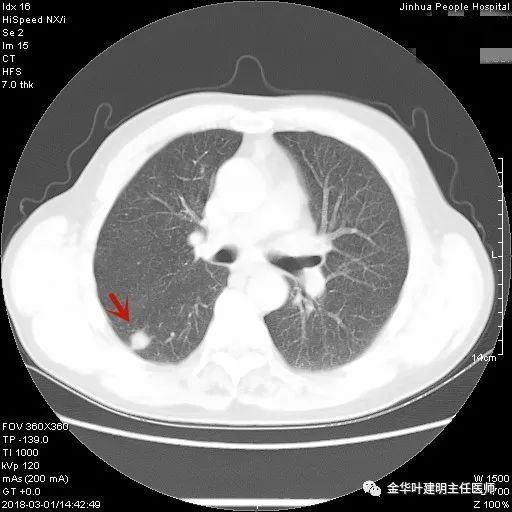

上图示胶原结节。我的理解是较慢性炎更向纤维瘢痕钙化发展,但仍未达钙化程度的一种状态(我不知道病理是不是这样)。该病灶表现为小而密度高的结节,边缘清晰,邻近胸膜却不牵拉,没有收缩力。